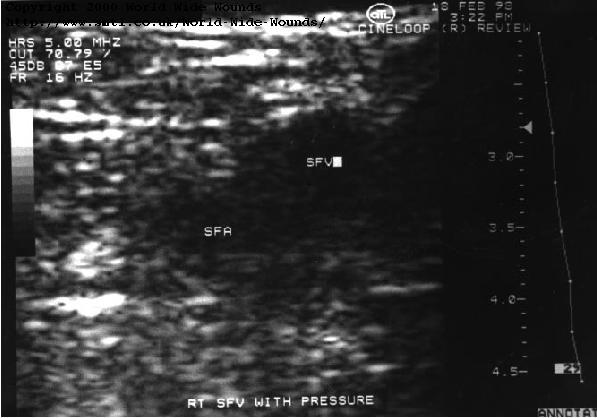

The examination starts in the groin. Transverse scanning is usually employed, and the probe is placed over the femoral vein. The patency of the vein is assessed from the colour display, but no augmentation of the flow is used because this could dislodge any thrombus that might be present. The probe is then pressed into the skin and compression of the vein is usually seen. It should be possible to completely compress the vein at the groin since it is near the surface. Any residual non-compressible lumen is likely to be filled with clot, and a careful examination of the region of flow on the transverse scan can help to confirm this. (Figure 19) shows a vein containing thrombus, and (Figure 20) shows the same vein failing to compress when probe pressure is applied.

[] Figure 19: Superficial femoral vein with thrombus. The thrombus can be seen as brighter echoes within the lumen of the vein and attached to the upper (anterior) wall.

[] Figure 20: Incompressible vein indicating thrombus. The vein (SFV) is not compressed when probe pressure is applied. This suggests a deep vein thrombosis which is confirmed when the vein is imaged longitudinally (Figure 19).